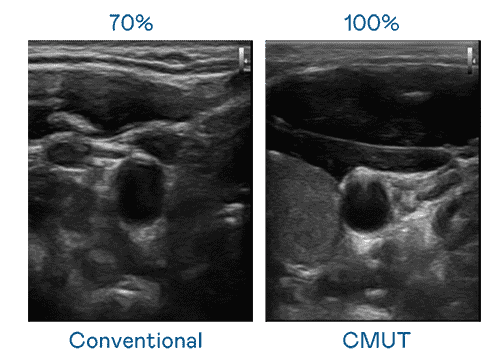

CMUT 技术是一种用电容式微机电元件来产生超音波讯号的技术。。。。与传统 PZT 压电式技术相比,,CMUT 频宽增加 30%,,,,更宽频的超音波讯号让影像解析度大幅提升,,是实现高影像品质医疗超音波扫描、、促进精准医疗发展的关键技术。。。。

大频宽带来超清晰影像

超音波影像的解析度高低,,,,首先取决于探头能发出的讯号频宽。。菠菜论坛 CMUT 可提供高清晰的超音波讯号,,提供高频宽、、、、高灵敏度、、、影像纹理细节更高的超音波影像,,,,协助医护人员缩短影像判读时间及利用精准的医疗影像进行诊断。。。。